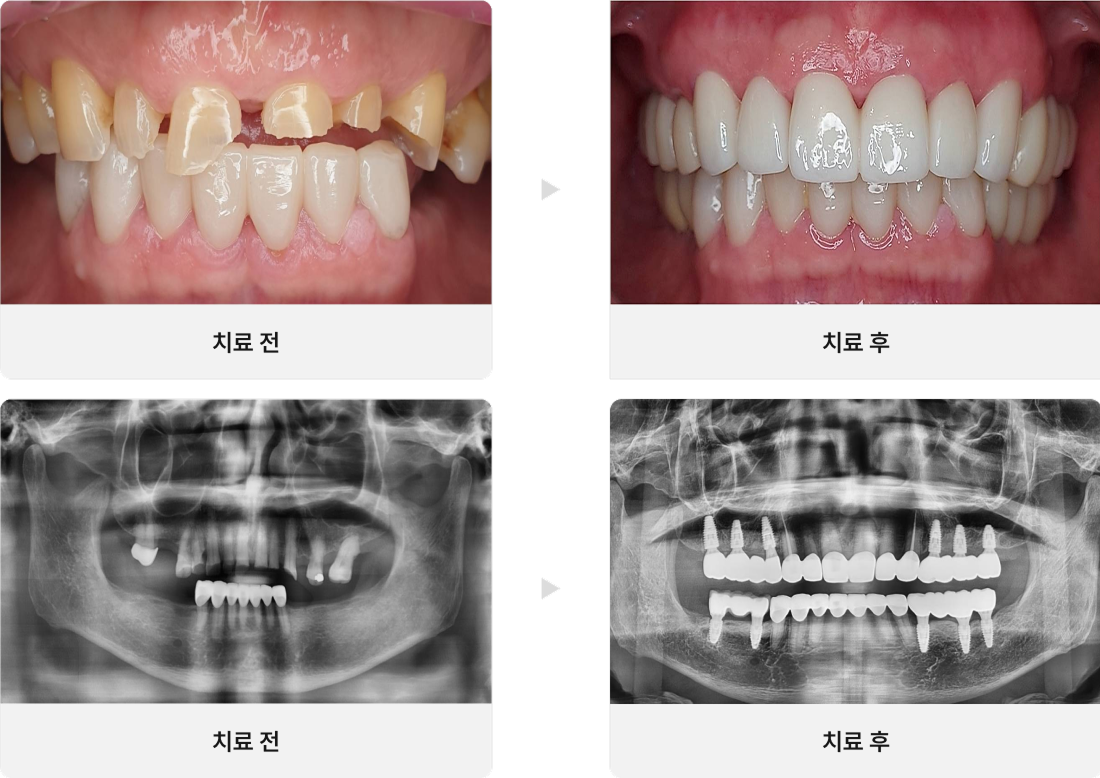

CASE.04

충치가 있는 치아 살리기